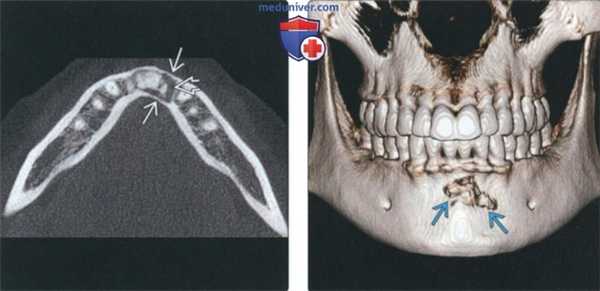

(Слева) На аксиальной КЛКТ у этого же пациента определяется истончение щечной и язычной кортикальных пластинок. Зона разрежения шире в дисталь -ных отделах, что позволяет заподозрить сопутствующую простую костную кисту.

(Справа) На трехмерной реконструкции (КЛКТ, вид спереди) у этою же пациента виден неровный контур патологическою очага, что позволяет оценить ею размеры. Интактная щечная пластинка истончена и не различима на КТ вследствие эффекта усреднения объема.

(Слева) На панорамной реформатированной КЛКТ определяется импактный третий моляр нижней челюсти слева с затемнением возле вершины корня в виде полумесяца (центральное образование цемента), окруженным линейным просветлением различной ширины (промежуточная стадия ПКД).

(Справа) На КЛКТ (профильный срез) у этого же пациента в области вершины корня моляра определяется типичный центральный рентгеноконтрастный участок в форме полумесяца, окруженный тонким линейным просветлением. Нижнечелюстной канал находится с щечной стороны от вершины корням.